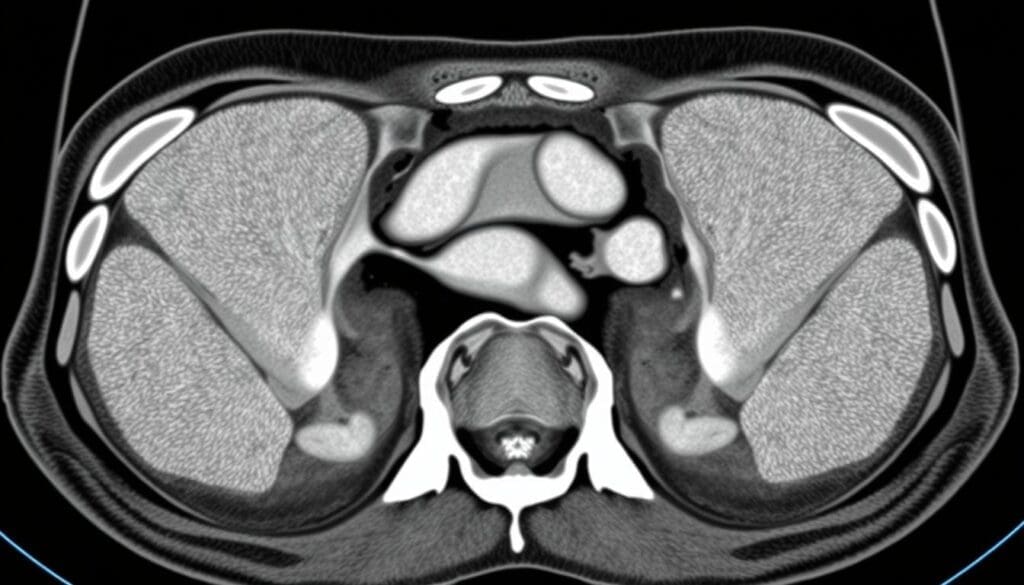

How CT Scans Work for Hernia Detection

CT scans are key in finding inguinal hernias. They use X-ray technology to show the body’s inside. This helps see the small details of the inguinal area and spot hernias.

Basic Principles of CT Imaging

CT scans mix X-rays and computer tech for detailed body images. The patient lies on a table that moves into a scanner. The scanner spins around, taking X-ray pictures from many angles.

These pictures are then put together into slices. This gives a full view of the body’s inside.

Specific Protocols for Hernia Evaluation

For finding hernias, special CT scan rules are followed. These rules help make the images clearer and more accurate. The Valsalva maneuver is often used. It’s when the patient tries to push air out with their mouth closed and nose pinched.

This makes it easier to see hernias. Thin-section imaging and multiplanar reconstructions also help. They let doctors see the inguinal canal and nearby areas well.

This helps them find hernias, know their size, and where they are. It also helps figure out any problems they might cause.